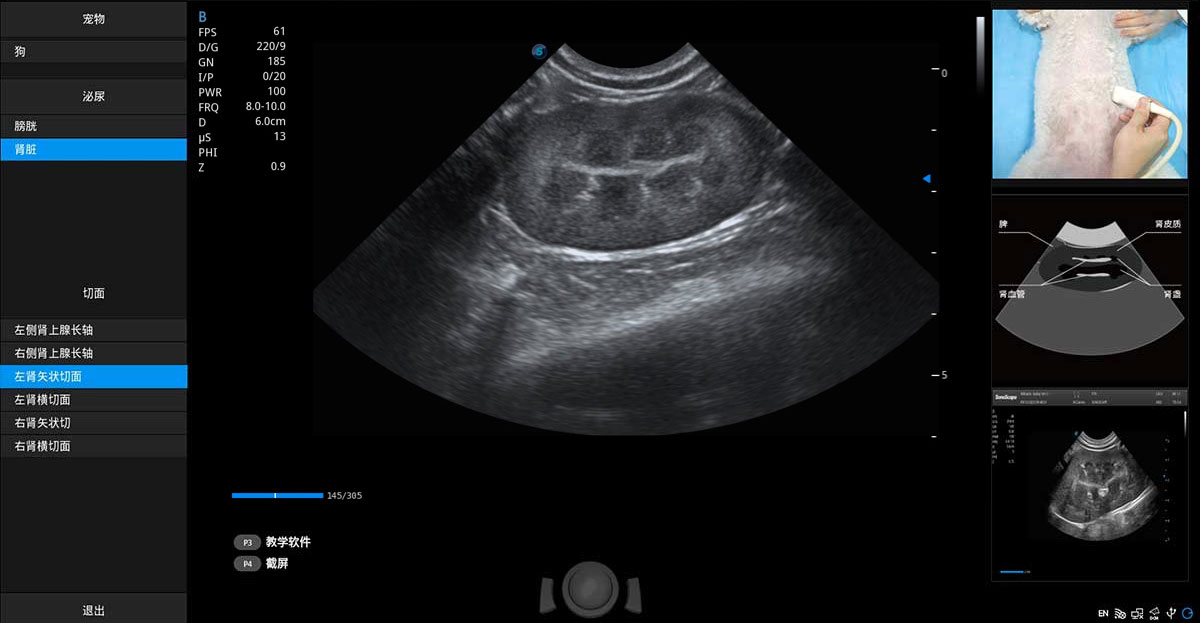

專業(yè)的動物影像專用軟件

ProPet 80 專為動物醫(yī)生設(shè)計,對不同的動物體型和生理結(jié)構(gòu)作出了針對性的優(yōu)化。通過動物影像專用軟件,可滿足個性化的應(yīng)用需求,幫助動物醫(yī)生獲得更精確的診斷數(shù)據(jù)。

• Sono Help 教學(xué)軟件

提供解剖示意圖、標(biāo)準(zhǔn)超聲圖像、掃查手法涂和操作者實時檢查圖像,指導(dǎo)操作者進(jìn)行標(biāo)準(zhǔn)切面的正確掃查。

(犬)腎臟顯微血流